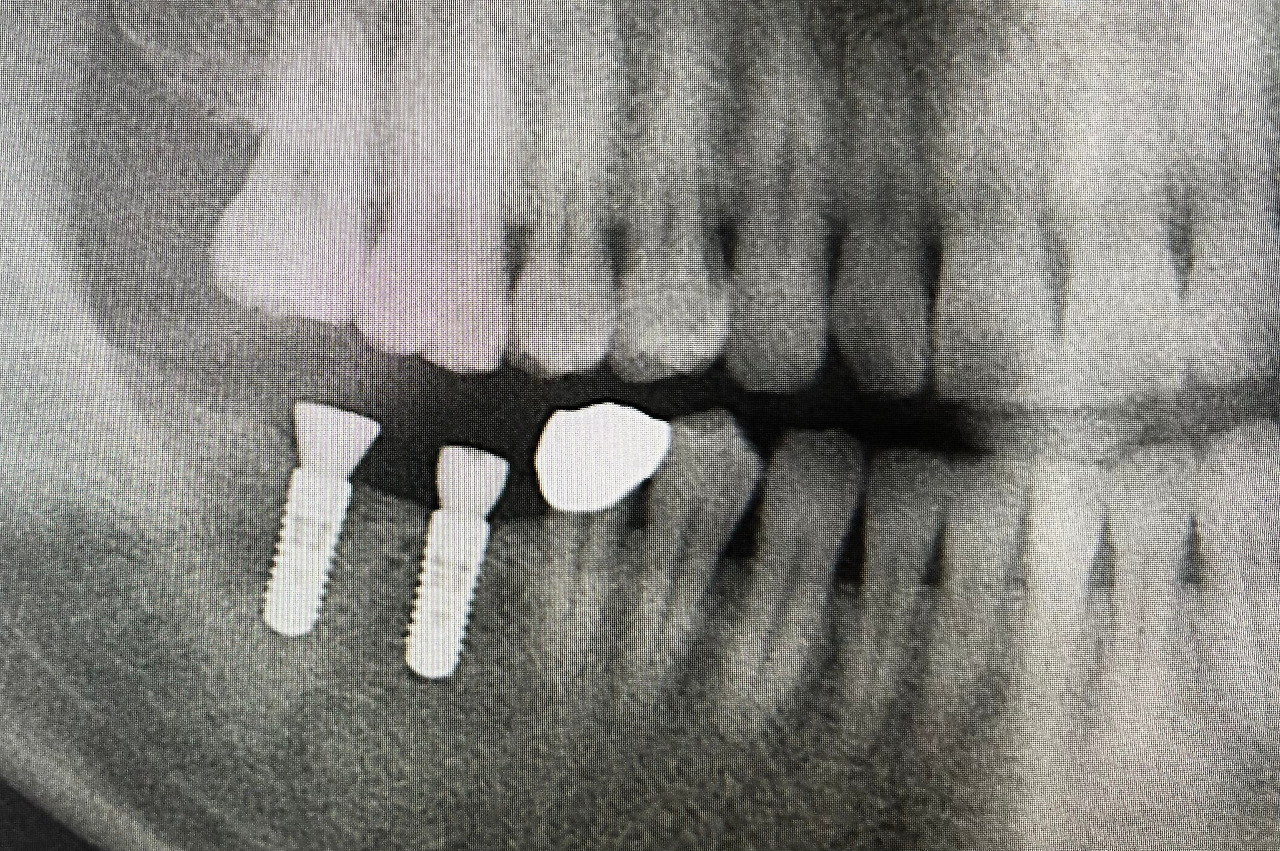

그 후로 20여 년이 넘게 잘 사용했으나 Abutment 어금니 뿌리가 부러지는 일이 있었고, 그 치아도 발치를 했어야 했었다. 자연스럽게 어금니 두 개가 없어진 채로 몇 개월을 지내야 했었다. 우습게도 이제야 정식으로 치료를 해야겠다는 생각을 했고, 친구 오피스를 찾았다. 내가 세운 treatment plan을 상담했고, 임플란트 두 개를 이식했다. 같이 일하는 후배의사한테 부탁해 크라운을 만들어 놓고 있었다. 시간이 많이 지났으나 적당한 시간을 찾지 못해 마무리를 하지 못하고 있었다. 환자분들한테는 언제나 우리가 제시하는 시간을 잘 지키라고 권유하지만 정작 나는 그러지 못했다. 차일피일 미루는 것이 숙제처럼 마음에 부담이 되었지만 한쪽으로만 먹는 것도 익숙해져서 시간은 일 년 가까이 지나고 있었다. 그러는 동안 다른 치아들이 부담으로 서서히 망가져 가는 것은 누구보다 더 잘 알면서.

그러다 그 친구랑 저녁 식사를 같이 하게 되었고 자연스럽게 내 임플란트 이야기가 나왔다. 아직도 마무리하지 않았다고 잔소리와 훈계를 한참이나 들어야 했다. 잔소리 들은 대가로 저녁을 사주고 늦은 저녁이었지만 바로 내 오피스로 그 친구를 납치해 갔다. 네가 시작한 거, 네가 마무리하라고 우기면서. 자정이 다가오는 시간이어서 주위에 아무도 없는 정적 가운데 둘이서 북 치고 장고치고를 시작했다.

그런데 그날 저녁 그 친구는 Loupe이 없었던 것이다. 저녁 먹다 갑자기 나한테 끌려온지라 Loupe 이 있는지 없는지 생각도 못한 것이었다. 내 것을 써보았지만 전혀 초점이 맞지 않아 도움이 되지 않았다. 돋보기 안경을 껴보아도 도움이 되지 않는다. 잠깐.. 둘 다 황당해하며 망설였지만… “What the heck, let’s do this. We have done this million times! “ 난 자신 있게 내 입을 벌리고 누웠고, 친구는 손가락 감각으로 Healing Abutments를 풀어내고, 또 손가락 감각으로만 새 치아의 Fit을 느끼면서 Torque Driver를 돌리고 있었다. 누워 있는 나는 알아서 Suction 위치를 잡고, Light Curing을 했다. ‘봉사가 코끼리 다리 만지듯’ 치아를 만지고 있었지만 입 안으로 들어오는 친구의 손가락의 위치만 느껴도 모든 게 정확했다. 군더더기 하나 없이.